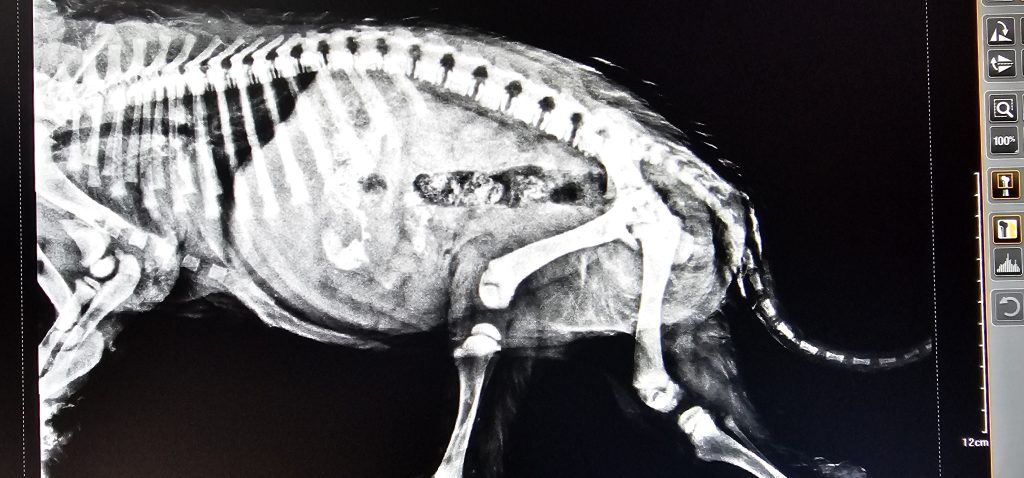

بخش تصویربرداری کلینیک آیرانا با استفاده از دستگاههای پیشرفته رادیولوژی دیجیتال و سونوگرافی تخصصی دامپزشکی، امکان ارزیابی دقیق ساختارهای داخلی بدن حیوانات را فراهم میکند

رادیولوژی برای بررسی مشکلات اسکلتی، قفسه سینه و نواحی شکمی کاربرد دارد و سونوگرافی، بهصورت مکمل، در تشخیص بافت نرم و ارزیابی اندامهایی مانند کبد، کلیه، معده، روده، رحم و مثانه نقش کلیدی دارد.